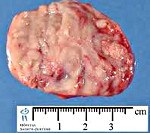

Патогномоничным генетическим дефектом при нейробластоме является потеря участка короткого плеча 1-ой хромосомы. У трети пациентов в опухолевых клетках обнаруживаются экспрессия либо амплификация N-myc онкогена, подобные случаи рассматриваются как прогностически неблагоприятные из-за быстрого распространения процесса и устойчивости неоплазии к действию химиопрепаратов. При микроскопии нейробластомы выявляются круглые мелкие клетки с темными пятнистыми ядрами. Характерно наличие очагов кальцификации и кровоизлияний в ткани опухоли.